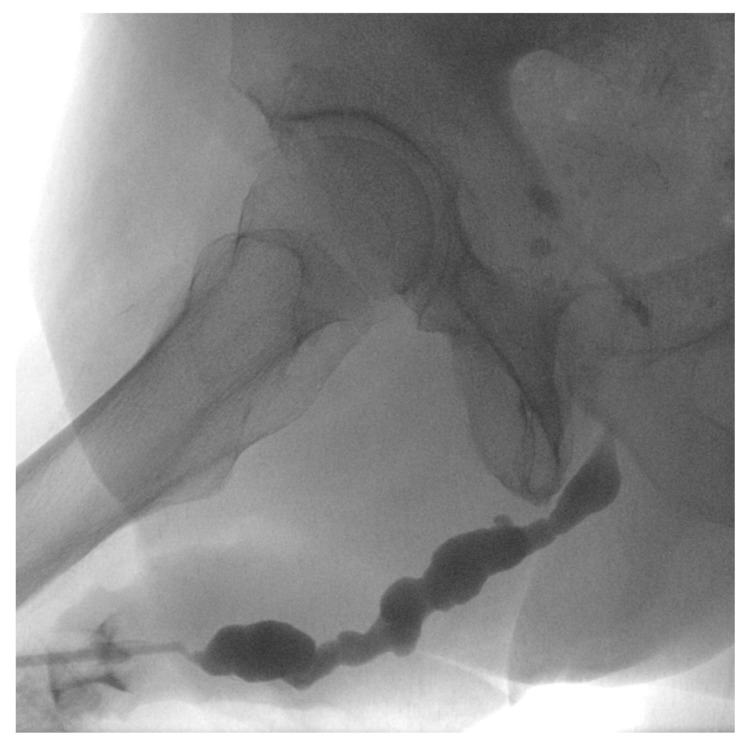

背景和目的:我们的目的是评估在复杂复发性尿道狭窄疾病治疗失败的患者中,前期Optilume药物包被球囊(DCB)扩张的结果。所有患者均出现急性尿潴留,无论狭窄部位和长度如何,均行DCB扩张治疗。材料和方法:我们回顾性评估急性尿潴留和已知复杂复发性尿道狭窄的患者。在2021年8月至2024年2月期间,无法排空或排空后残留(PVR)容量超过400ml的患者出现在我们三级中心的泌尿科急诊室。尿道造影和/或内窥镜成像证实了诊断。排除尿路感染/败血症患者和神经系统疾病患者。先行尿道扩张至20fr,然后行DCB扩张(30fr, 10bar, 10min)。主要终点是12个月时解剖成功(膀胱镜检查/校准≥14fr)和没有重复干预。结果:31例男性患者连续接受评估,其中26例随访≥12个月(平均年龄65±16.8岁)。狭窄部位包括球囊狭窄7个,球膜狭窄7个,吻合口狭窄7个,膀胱颈狭窄3个,阴茎狭窄1个,全尿道狭窄1个。既往尿道/手术干预的中位数为2例[IQR: 1-3](范围:1-31)。中位狭窄长度为3 [IQR: 2-4] cm(范围:1-8)。12个月时,65.4%(17/26)的患者手术成功,无复发和再手术。结论:对于复杂复发性尿道狭窄和尿潴留患者,特别是不能或不愿进行手术重建且不愿留置导尿管的患者,及时行DCB扩张可能是一种可行的治疗选择。

Background and Objectives: We aimed to assess the outcomes of upfront Optilume drug-coated balloon (DCB) dilation in patients after failed treatment for complex recurrent urethral stricture disease. All patients presented with acute urinary retention and were treated with DCB dilation regardless of stricture site and length. Materials and Methods: We retrospectively evaluated patients with acute urinary retention and known complex recurrent urethral strictures. Patients presented at the urology emergency room of our tertiary centre with an inability to void or a post-void residual (PVR) volume exceeding 400 mL between August 2021 and February 2024. Urethrography and/or endoscopic imaging confirmed the diagnosis. Patients with urinary tract infection/sepsis and those with neurological disease were excluded. Urethral dilation to 20 Fr was performed, followed by DCB dilation (30 Fr, 10 bar, 10 min). The primary endpoints were anatomical success (≥14 Fr by cystoscopy/calibration) at 12 months and freedom from repeat interventions. Results: Thirty-one consecutive male patients were evaluated, with twenty-six patients followed for ≥12 months (mean age 65 ± 16.8 years). The stricture sites included seven bulbopenile, seven bulbomembranous, seven anastomotic, three bladder neck, one penile, and one panurethral stricture. The median number of prior urethral/surgical interventions was 2 [IQR: 1-3] (range: 1-31). The median stricture length was 3 [IQR: 2-4] cm (range: 1-8). At 12 months, 65.4% (17/26) of subjects voided satisfactorily and were free of recurrence and reoperation. Conclusions: Timely DCB dilation may offer a viable treatment option for patients with complex recurrent urethral strictures and urinary retention, particularly those who are unable or unwilling to undergo surgical reconstruction and prefer to avoid indwelling catheters.